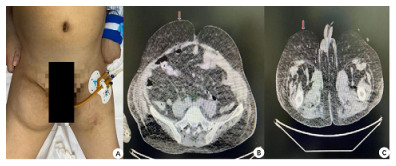

入院查体:患者呈昏迷状,双侧瞳孔等大等圆,直径3 mm,对光反射迟钝,颈部(图 1)和肩部(图 2)分别可见7 cm×4 cm及5 cm×6 cm大小软组织肿胀,质软,腹部及双侧大腿内侧(图 3)可见5 cm×6 cm软组织肿胀,质软,双肺呼吸音粗,双肺可闻及少许湿啰音,心律齐,各瓣膜听诊区未闻及病理性杂音,腹部膨隆,腹部查体不配合。入院后相关检查见表 1,腹部超声提示脂肪肝,心脏超声示左室壁运动弥漫性减低、左室壁肥厚,左室射血分数47%。

| A:患者腹部及双侧大腿内侧对称性脂肪隆起;B:下腹部CT平扫(轴位-下腹部皮下脂肪影增多);C:患者下腹部CT平扫(轴位-双侧大腿内侧皮下脂肪影增多) 图 3 患者下腹部及双侧大腿内侧病变(红色箭头所示) |